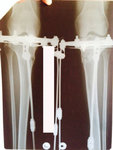

Рентген в 90 дней.

Здравствуйте,Rozali! Приезжайте на снятие аппаратов. Всё отлично! Пересрослось!!!Здравствуйте. Высылаю снимки. Как сращение? Могу приезжать на снятие?